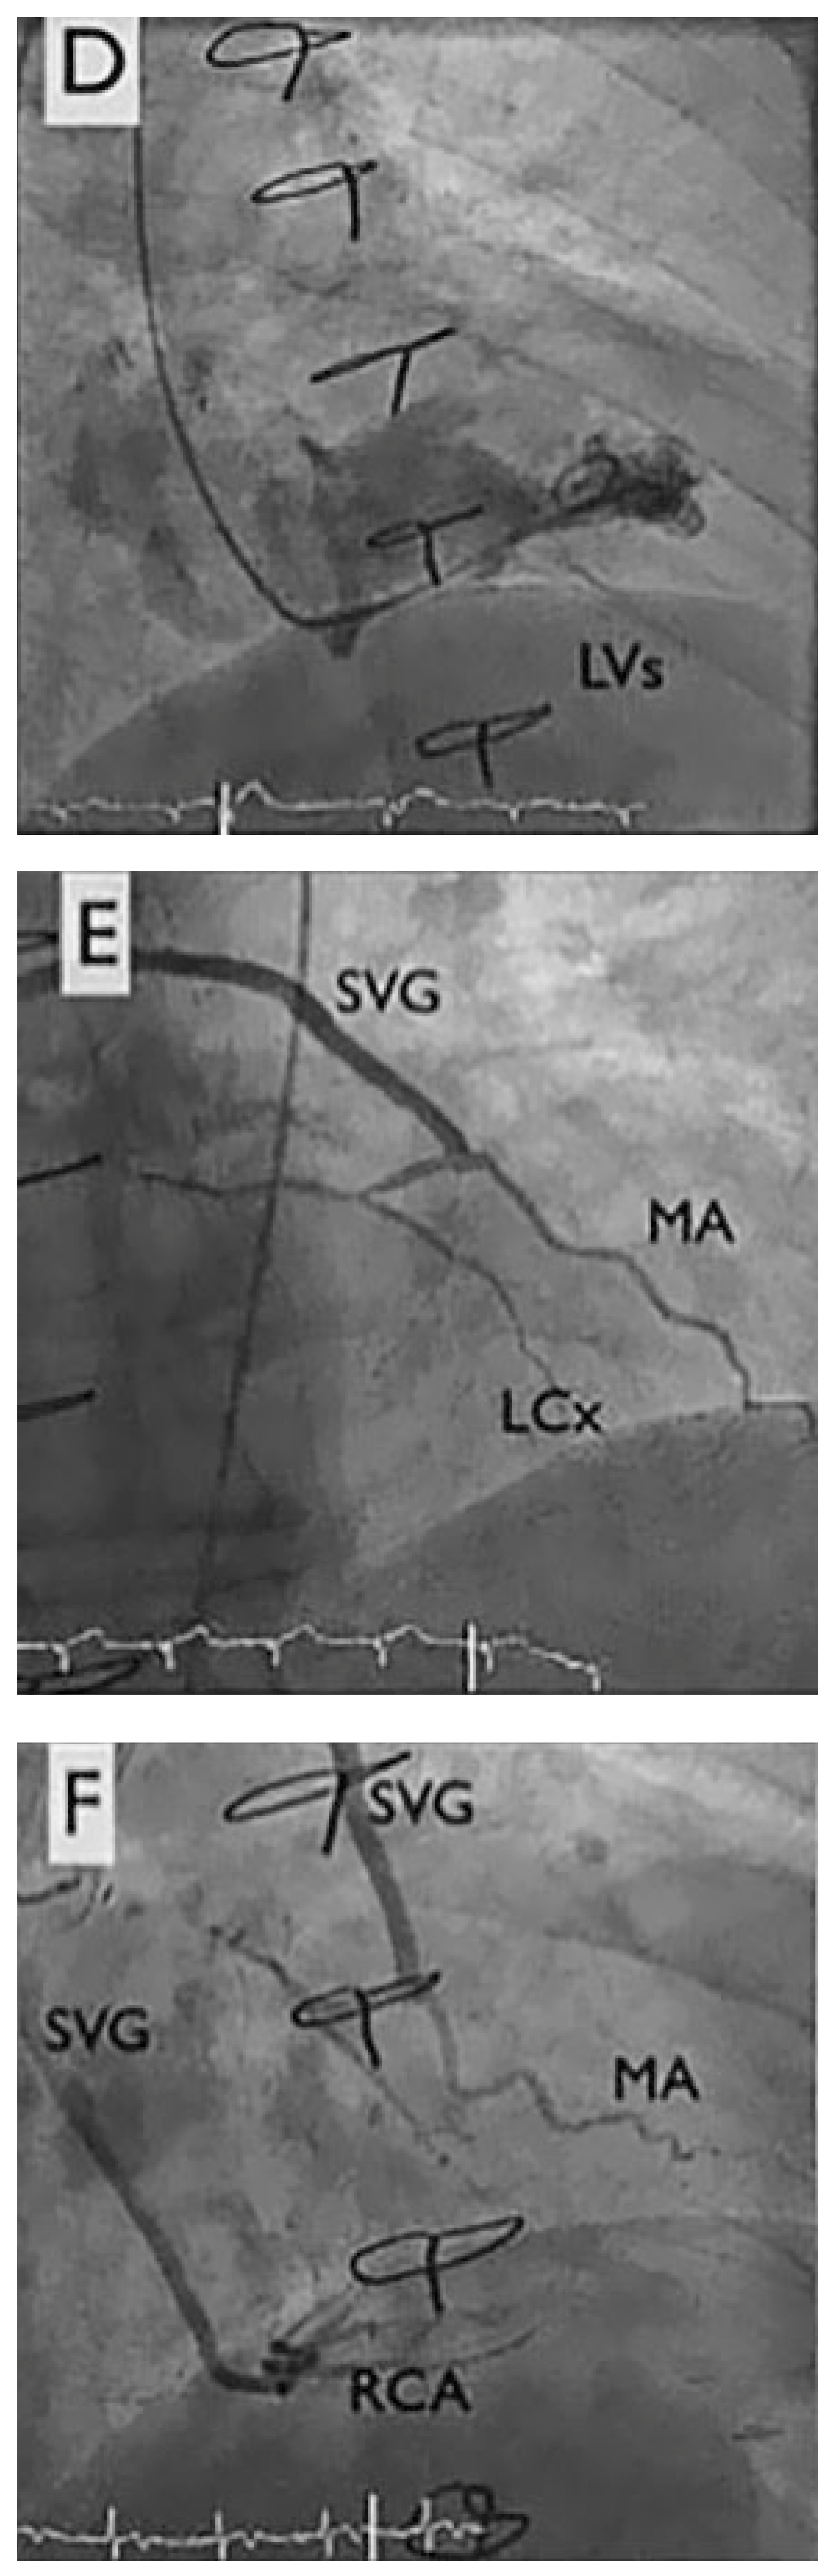

A 67-year-old diabetic patient with three-vessel coronary artery disease (Figure 1) and prior coronary artery bypass graft surgery (left internal mammary artery to left anterior descending artery, vein to marginal branch, vein to right coronary artery) suffered from refractory angina. Coronary angiography demonstrated good results after surgical revascularisation, but also a diffuse infiltration of the left coronary tree. Left ventricular systolic function was normal. The patient presented refractory angina despite optimal antianginal therapy comprising beta-blockers, nitrates, ranolazine (Ranexa®) and molsidomine (Corvaton®). The patient was severely disabled, being unable to walk 200 metres without nitrates, and waking up every 2 hours because of angina and paroxysmal dyspnoea. The treadmill test showed ischaemia.

Figure 1.

Coronary angiogram. LAD: left anterior descending artery, LCx: left circumflex artery, LIMA: left internal mammary artery, MA: marginal artery, RCA: right coronary artery, ous vein graft; LVS: left ventricular tele-systolic volume; LVD: left ventricular tele-diastolic volume.